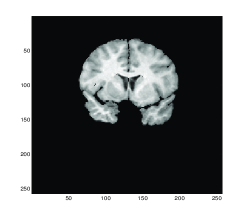

For comparison, the transformed template images for the diffeormorphic demon method, linear, mean and Gaussian curvatures are shown in Figures 2 (a), (b), (c) and (d) respectively. We can observe that there are some differences of these images inside the red boxes where only Gaussian curvature delivering the best result of the features inside the boxes.

Refer to caption

(a) Model D

(b) Model LC

(c) Model MC

(d) Gaussian curvature

Figure 2: Test 1 (X-ray hand). Comparison of Gaussian curvature with competing methods. The transformed template image using (a) Model D, (b) Model LC, (c) Model MC and (d) Gaussian curvature. Note the difference of these three images inside the red boxes.